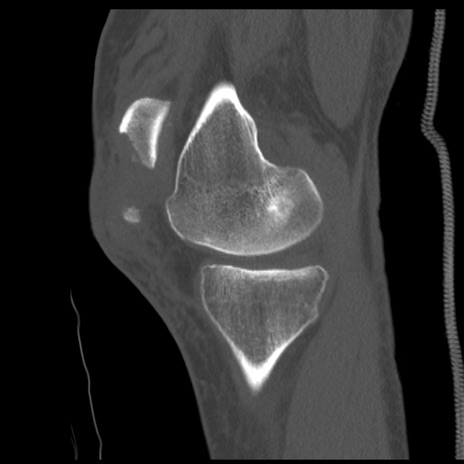

症例28 右膝関節CT(矢状断像)

右膝関節CT